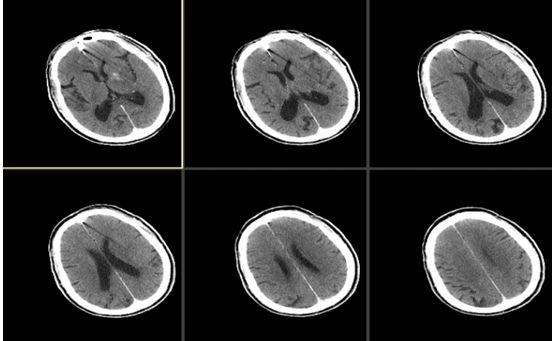

溶栓前头颅平扫CT检查未见明显新发病灶(图1),ASPECTS评分:10分

图1

溶栓后复查头颅CT检查未见出血,但左侧大脑中动脉有高密度征(图2)。

图2

术后复查头颅平扫CT可见左侧基底节区局部造影剂滞留(图8)

图8